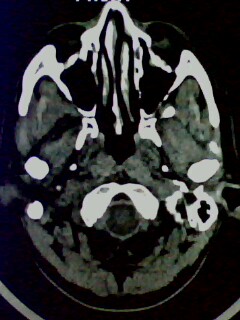

以下是引用随光逐影在2009-5-20 19:22:00的发言:[br]1)考虑左上颌骨近中线区含牙囊肿。2)鼻中隔右突偏曲。3)双侧下鼻甲肥大。